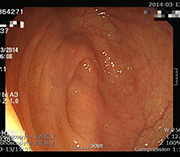

潰瘍性大腸炎前後の粘膜回復

腸粘膜のひどい炎症、発赤、潰瘍が治まり、滑らかで健康な状態に回復した事例です。

事例 1

治療前 治療前 腸内粘膜写真

治療後 治療後 腸内粘膜回復写真